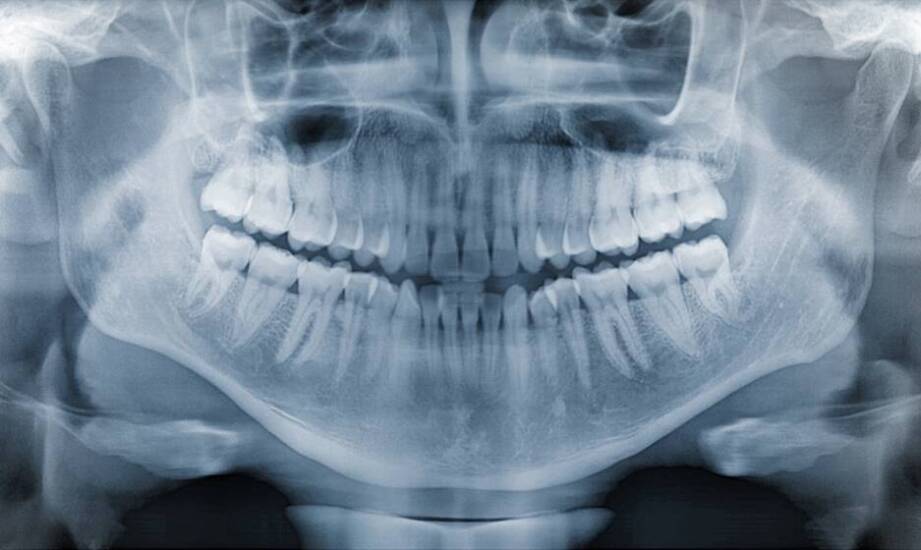

RTG zębów to narzędzie w diagnostyce stomatologicznej, umożliwiające wykrywanie zmian w jamie ustnej. Z wykorzystaniem technologii obrazowania, takich jak tomografia stożkowa, lekarze mogą uzyskać szczegółowe obrazy anatomiczne, co wspiera proces leczenia. Uzyskane informacje mogą ułatwiać dobór dalszego postępowania terapeutycznego. W artykule omówimy, jak RTG zębów jest wykorzystywane w postępowaniu przy stanach zapalnych oraz inne aspekty tego badania w kontekście leczenia problemów stomatologicznych, ze szczególnym uwzględnieniem praktyk w Sopocie.

Punktowe RTG zęba to badanie obrazowe, które pozwala ocenić stan zębów oraz tkanek otaczających. W przypadku podejrzenia stanów zapalnych jest to element diagnostyczny. Dzięki niemu specjaliści mogą identyfikować problemy takie jak ropnie czy infekcje, co umożliwia podjęcie odpowiednich działań terapeutycznych. Badanie to ma znaczenie przed ekstrakcją zęba, gdyż pozwala ocenić stan korzeni oraz ewentualne zagrożenia dla sąsiednich struktur. RTG zębów w Sopocie oraz w innych miastach jest dostępne w różnych placówkach stomatologicznych oferujących zakres usług dentystycznych. Badanie może być wykonywane m.in. w przypadku wystąpienia bólu czy obrzęku w jamie ustnej, w ramach diagnostyki.

Tomografia stożkowa (CBCT) to technika obrazowania, która dostarcza trójwymiarowych obrazów struktur anatomicznych. Dzięki tej technologii lekarze mogą dokładniej ocenić rozległość stanów zapalnych oraz ich wpływ na sąsiednie tkanki, co może wspierać planowanie leczenia. W przypadku stanów zapalnych w jamie ustnej tomografia CBCT umożliwia identyfikację problemów dotyczących dziąseł i przyzębia oraz ocenę stanu korzeni zębów. Dzięki temu specjaliści mają możliwość doboru metod terapeutycznych, takich jak leczenie kanałowe czy chirurgia stomatologiczna. rtg zębów w Sopocie to badanie dostępne w Sopocie. Informacje uzyskane w tomografii CBCT mogą stanowić element diagnostyki i terapii problemów stomatologicznych, a jej zastosowanie w praktyce stomatologicznej jest coraz bardziej powszechne.

Interpretacja wyników RTG w kontekście terapii